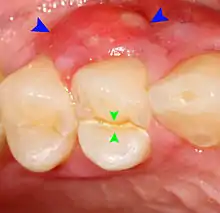

Decay (green) with apical abscess (blue)

Gutta-percha point indicating abscess origin